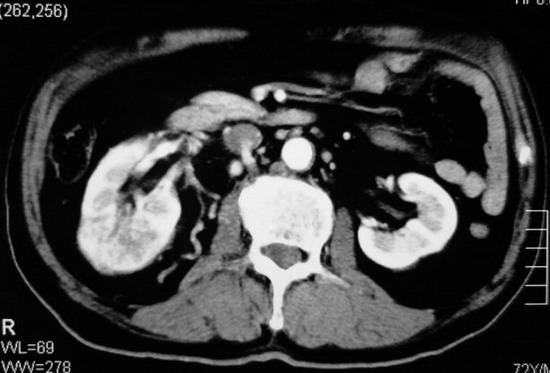

以下是引用杀毒软件在2008-11-17 19:15:00的发言:[br]考虑------右肾癌合并肾静脉---同侧肾上腺受侵可能性大

以下是引用zjzjr在2008-11-17 20:45:00的发言:[br]考虑------右肾癌合并肾静脉---同侧肾上腺受侵可能性大及腹膜后淋巴结转移.